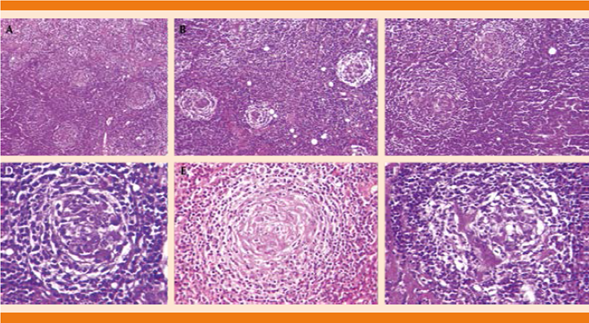

Biopsia incisional de tumor retroperitoneal: tejido linfoide maduro, compatible con linfoma no Hodgkin con granulomas tipo Castleman. Con segunda interpretación en el Servicio de Patología el reporte fue de ganglio linfático con enfermedad de Castleman variedad hialino-vascular (Figura 3).

Figura 3 Ganglio linfático que muestra hiperplasia folicular. Fotos panorámicas en las que se observan folículos linfoides de diferentes tamaños (A, B, C). A mayor detalle se observan capas concéntricas de linfocitos en la periferia de los centros germinales, con aspecto en tela de cebolla (D, E), así como vasos de pared hialinizada en el centro de un folículo linfoide (F).

La paciente se diagnosticó con la variedad histológica del subtipo hialino vascular. Este subtipo es el más frecuente y se caracteriza por folículos con centro germinal atrófico, rodeado de una zona de manto prominente (con pequeños linfocitos). Los centros germinales generalmente no contienen linfocitos, sino una población residual de células dendríticas que frecuentemente expresan CD21, CD23, CD35, y el receptor de factor de crecimiento epidermoide. La morfología característica por las células dendríticas se conoce como “en capa de cebolla”.13,14